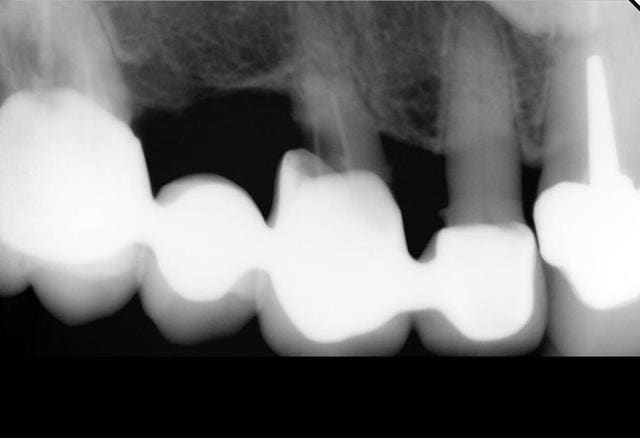

J'ai besoin d'avis éclairés pour une patiente dont voici la situation initiale:

- Femme de 83 ans qui consulte pour le rescellement de 44 avec 43 en extension collé au gros composite sur 42.

Voici le compte -rendu de mon bilan:

. Maxillaire: 18 incluse

- bridge 16 à 12 (sans 15) avec carie sur 13 et 12 vitale (ou du moins pas d'endo)

- couronne sur 11

- bridge 21 à 25 avec caries sur 21 et 23

- 27 RAS, absence de 17 et 26 non remplacées

.Mandibule: 44/43 à refaire, 35 à 37 non remplacées, crête pas très épaisse derrière 34, problème paro (présence de tartre)

Les bridges du haut sont donc perdus, 13, 21 et 23 à extraire, dents restantes ensuite: 16,12,11,25,27

Je vous met les radios et j'attend vos avis avec impatience.